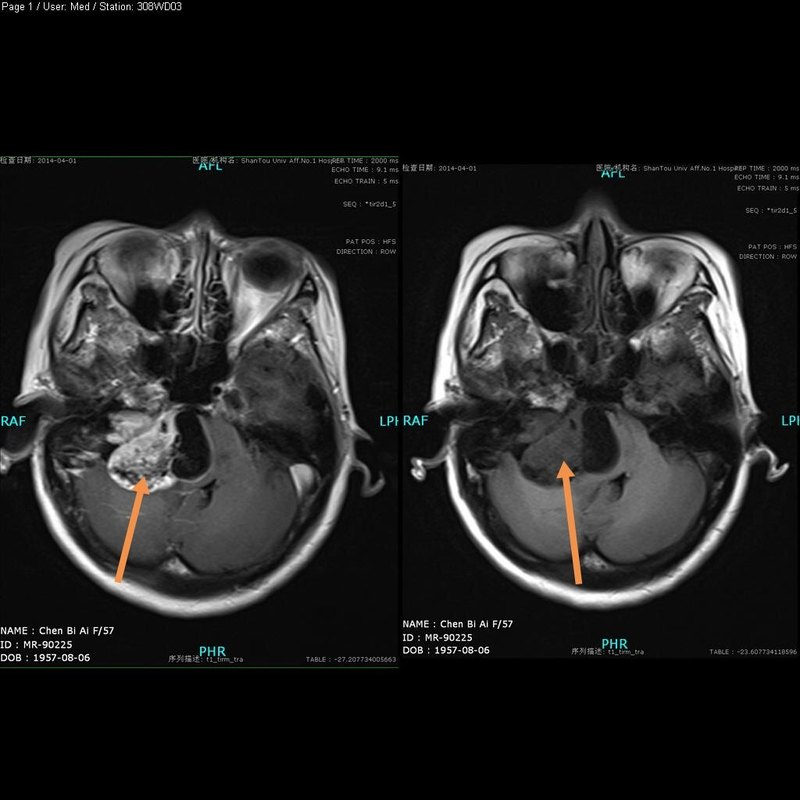

反復(fù)抽搐3年、左側(cè)肢體乏力半年。 患者3年前出現(xiàn)肢體抽搐,外院就診,顱腦核磁共振檢查診斷矢狀竇旁腦膜瘤,建議手術(shù)治療,病人對手術(shù)風(fēng)險不能接受,行伽瑪?shù)吨委煟肽旰髲?fù)查,腫瘤沒有變化,再次行伽瑪?shù)吨委?,肢體抽搐仍反復(fù)發(fā)作,藥物治療不能完全控制,近半年來發(fā)作頻繁,并出現(xiàn)左側(cè)肢體乏力,不能站立、走路。 體檢:神清,左側(cè)肢體肌力II~III級。 顱腦核磁共振檢查結(jié)果如下圖: 入院后予術(shù)前準(zhǔn)備,在全麻下行開顱腫瘤切除手術(shù),手術(shù)順利,腫瘤完全切除,術(shù)后得到癲癇控制,左側(cè)肢體肌力逐漸恢復(fù),生活能自理。 術(shù)后復(fù)查核磁共振如下圖: 點評:腫瘤位于中三分之一矢狀竇旁、中央前回(運動中樞)處,術(shù)前病人已經(jīng)出現(xiàn)偏癱,經(jīng)過兩次伽瑪?shù)吨委熀笈c周圍腦組織緊密粘連,周圍腦組織嚴重水腫,手術(shù)時容易損傷正常腦組織致后遺癥,本手術(shù)成功切除腫瘤,且保護了正常腦組織,病人左側(cè)肢體功能得以恢復(fù)。